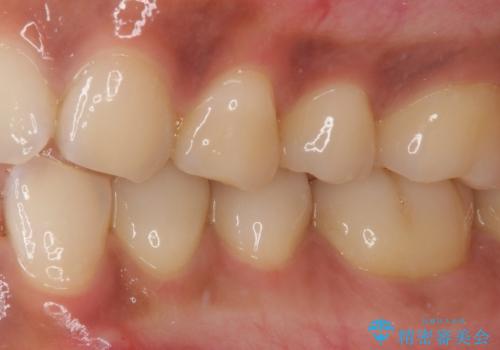

痛みでうずく 根管治療と補綴治療

- 下顎の小臼歯が食事などの度に痛みを感じるとのことで来院された患者様です。

レントゲン写真などで診査を行ったところ、左下の第一小臼歯の神経組織が壊死し、根尖部周辺の骨に炎症が認められました。

まずは根管治療を行い、症状が消退したことを確認してオールセラミッククラウンにて補綴治療を行うこととしました。